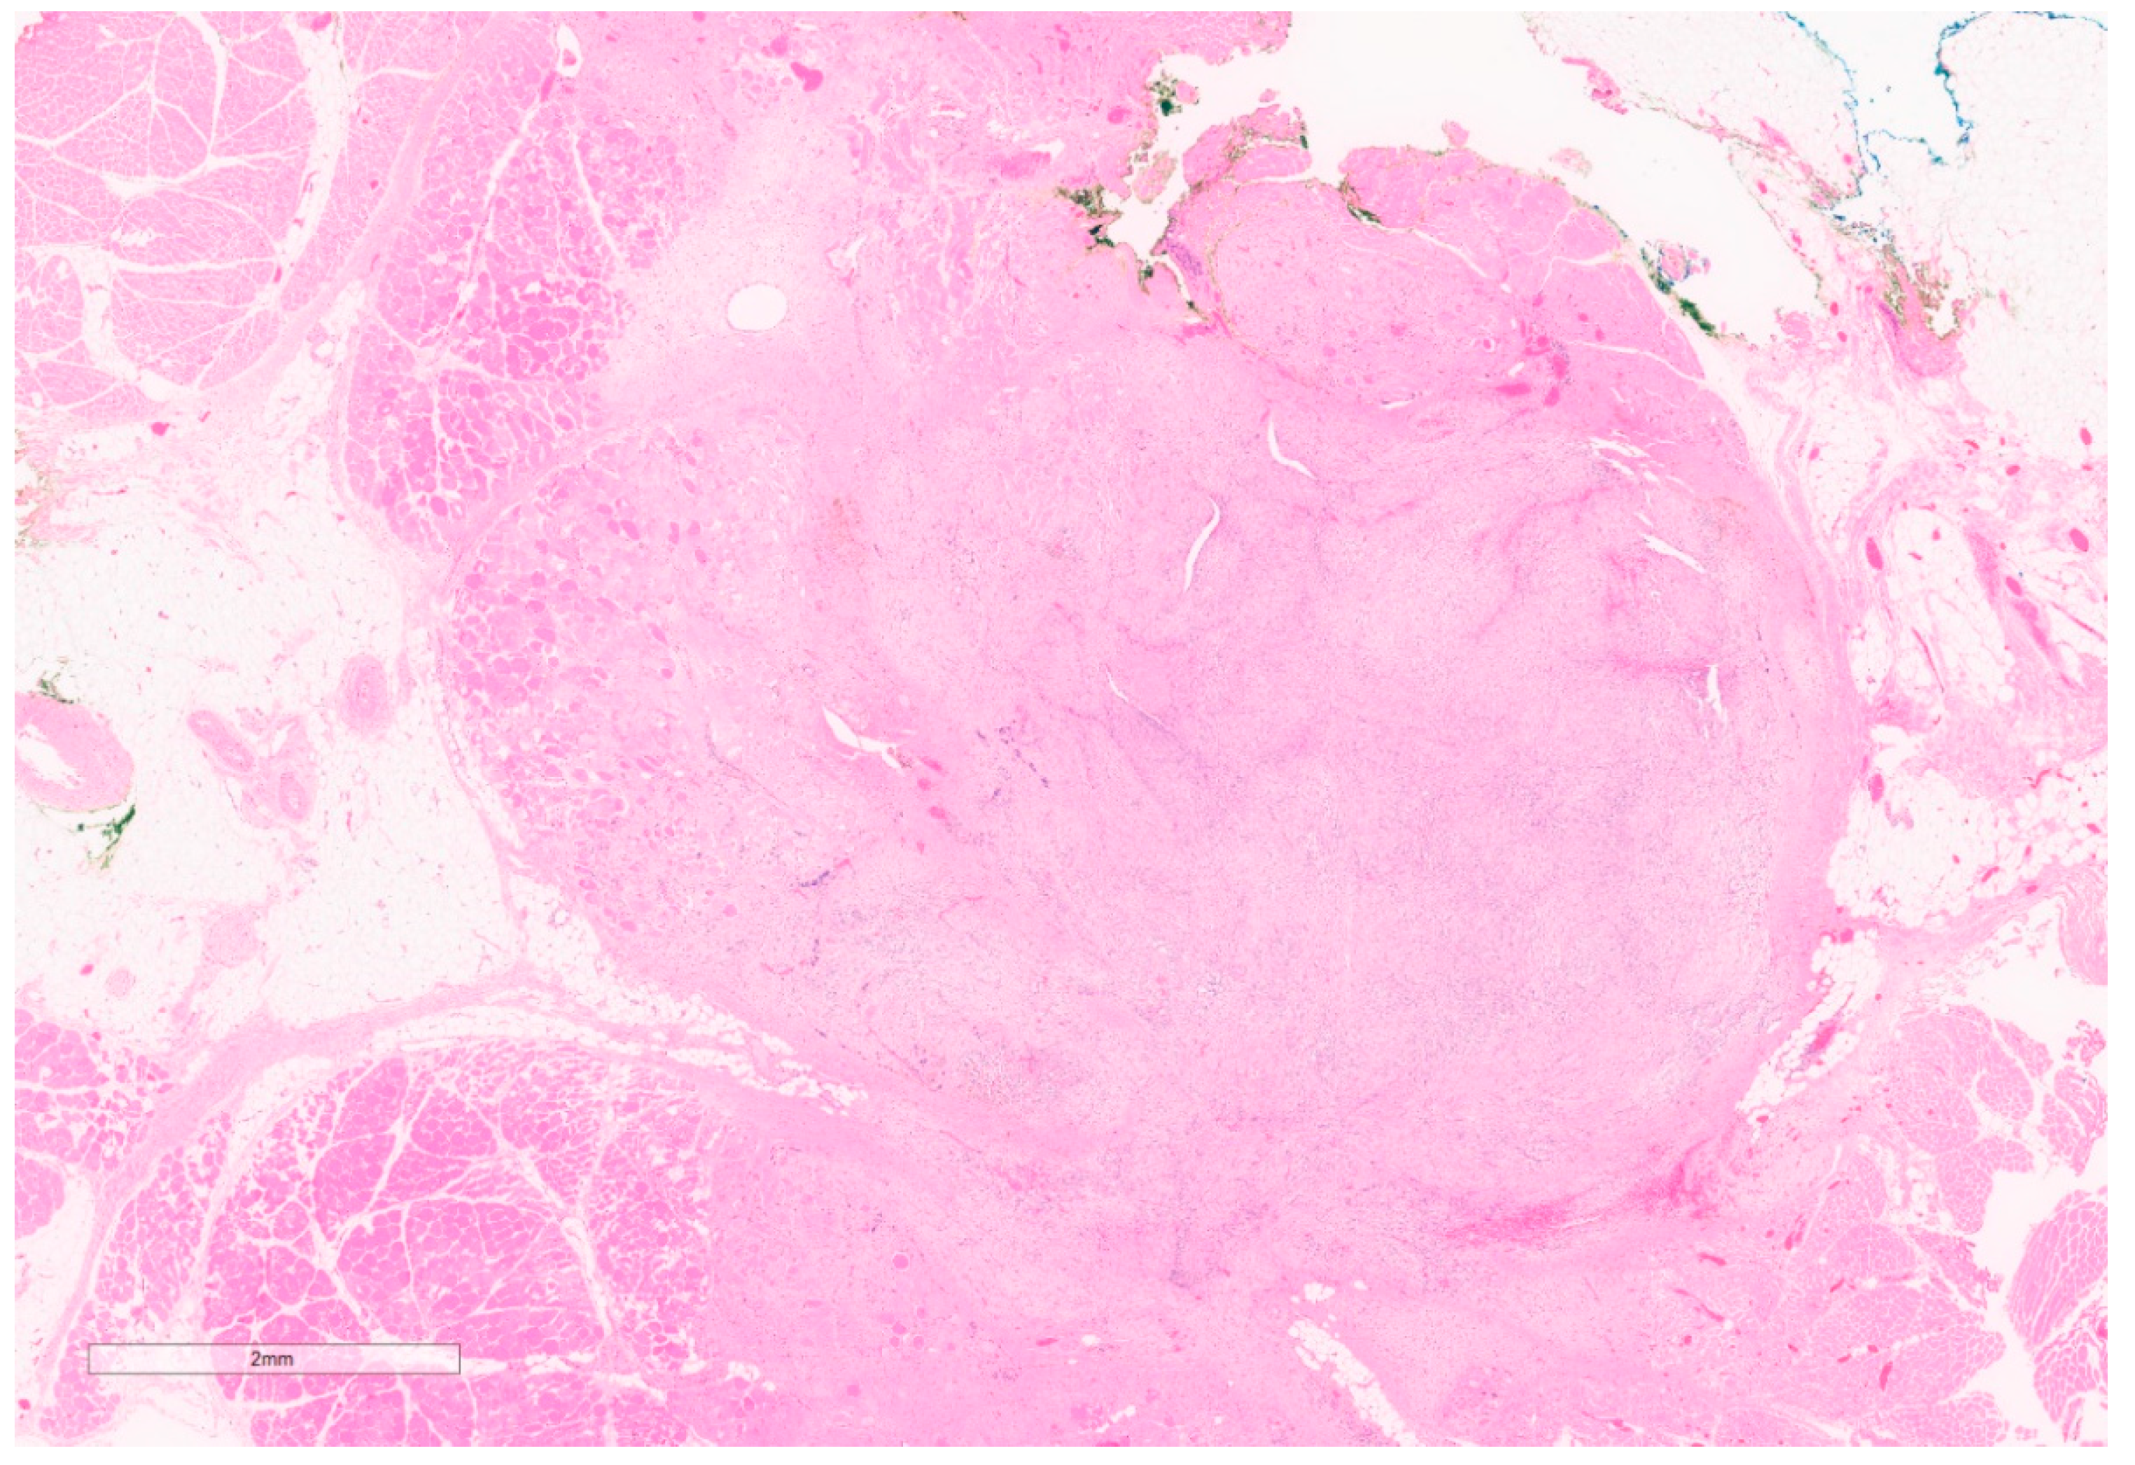

2.3. Fibromatosis/Desmoid Tumor

Summary of Updates